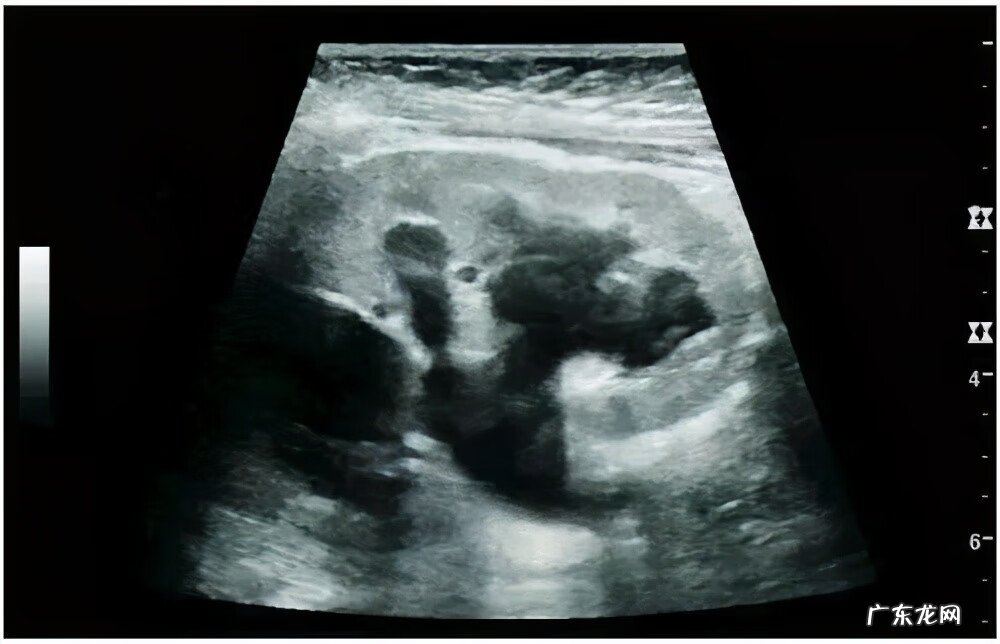

肾脏B超可清晰显示肾积水情况,明确有无结石,了解肾盂、肾盏等结构,简单、方便、无创